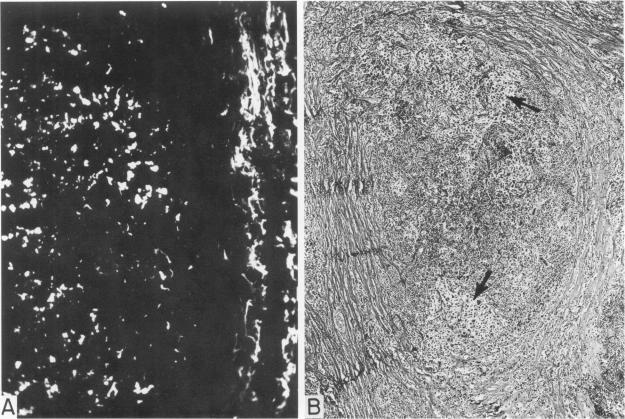

Fibrin deposits were observed in the involved lymph nodes and/or spleens of 15 patients with Hodgkin's disease by specific immunofluorescence and by electron microscopy. Two basic patterns of fibrin deposition were observed: 1) intercellular deposits, chiefly associated with nonneoplastic-appearing lymphoid cells and 2) deposits associated with the collagen fibers of young connective tissue. In addition, coarse fibrin deposits were observed in areas of necrosis, presumably a non-specific finding. Fibronectin was also observed in intercellular areas, but staining was less intense than for fibrin. Fibrin deposits were also observed in 3 of 6 cases of non-Hodgkin's lymphoma, indicating that the finding is not an exclusive feature of Hodgkin's disease. The pathogenesis and possible significance of fibrin deposition in Hodgkin's disease are related to earlier observations of activation of the coagulation system on neoplasia and cell-mediated immunity and to the possible role of fibrin, fibronectin, and their breakdown products in angiogenesis and fibroplasia.

通过特异性免疫荧光和电子显微镜观察,在15例霍奇金病患者受累的淋巴结和/或脾脏中发现了纤维蛋白沉积。观察到两种基本的纤维蛋白沉积模式:1)细胞间沉积,主要与外观无肿瘤特征的淋巴细胞相关;2)与年轻结缔组织的胶原纤维相关的沉积。此外,在坏死区域观察到粗大的纤维蛋白沉积,这可能是一个非特异性发现。在细胞间区域也观察到纤连蛋白,但染色强度低于纤维蛋白。在6例非霍奇金淋巴瘤中,有3例也观察到纤维蛋白沉积,这表明该发现并非霍奇金病的独有特征。霍奇金病中纤维蛋白沉积的发病机制及可能意义与先前关于肿瘤形成时凝血系统激活和细胞介导免疫的观察结果有关,也与纤维蛋白、纤连蛋白及其降解产物在血管生成和纤维形成中可能发挥 的作用有关。